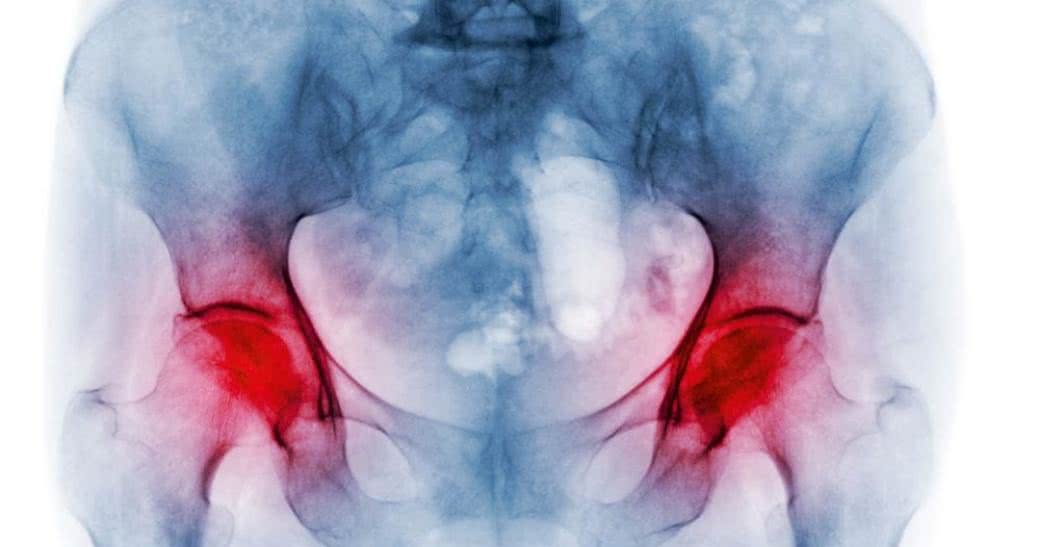

Standardem diagnostyki osteoporozy pozostaje densytometria, czyli pomiar gęstości mineralnej kości (bone mineral density, BMD) w obrębie kręgosłupa i nasady bliższej kości udowej. Według wytycznych Światowej Organizacji Zdrowia (WHO) chorobę rozpoznaje się, gdy wynik tego badania jest mniejszy o co najmniej 2,5 odchylenia standardowego od szczytowej masy kostnej zdrowych dorosłych w młodym wieku (wskaźnik T-score ≤ -2,5).